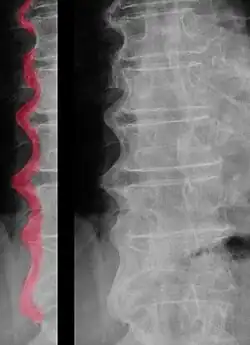

É principalmente caracterizada pela produção excessiva de tecido ósseo na zona das articulações, levando à calcificação das enteses e dos ligamentos.[2][3] Esta atividade de osteossíntese anormalmente elevada é particularmente observável nos ossos da coluna vertebral, por baixo do ligamento longitudinal anterior. No entanto, na região das vertebras torácicas, a formação anormal de osso é limitada ao lado direito destas.[2] Pensa-se que este fenómeno estará associado ao facto de a artéria aorta se localizar do lado esquerdo dos corpos vertebrais torácicos.[2][6]

Em estudos paleopatológicos, existem vários métodos para o diagnóstico da DISH: e.g. Crubézy (1989), Crubézy e Crubézy-Ibanez (1993) e Rogers e Waldron (1995).[24] Todos estes métodos têm em comum considerarem não só as lesões da coluna mas também a calcificação das enteses e apresentam como critério obrigatório a ossificação ântero-lateral da coluna com preservação da articulação apofisária.[6] Destes métodos, o mais exigente, pelo maior número de características, é o de Rogers e Waldron, que em 2001,[25] resumiram o seu método de diagnóstico a três critérios obrigatórios para o diagnóstico de DISH: a presença de hiperostose da coluna, afetando pelo menos três vértebras; modificações ósseas da zona torácica da coluna restringidas ao lado direito desta (com exceção de raros casos de situs inversus) e presença de calcificações e/ou ossificações de ligamentos e/ou enteses extra-raquidianas. Estes autores consideraram que a preservação da altura dos discos intervertebrais não deveria ser utilizado como critério de diagnóstico, apenas como corroboração deste.[2][3][25]